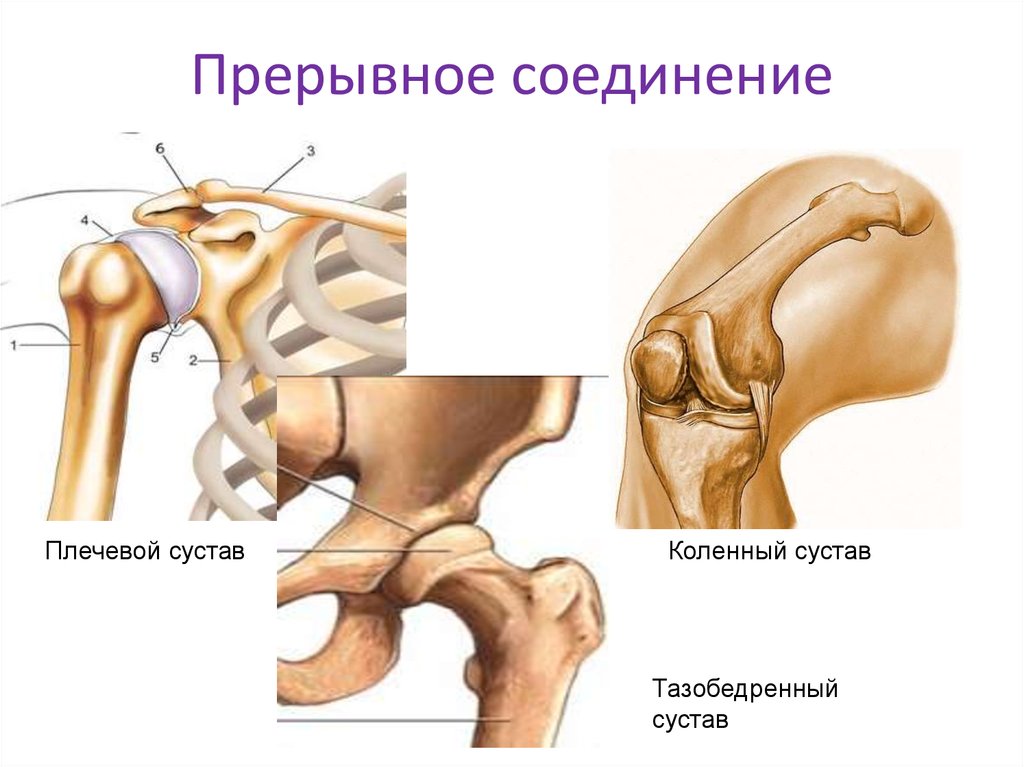

Диаграммы и схемы движения в суставах человека